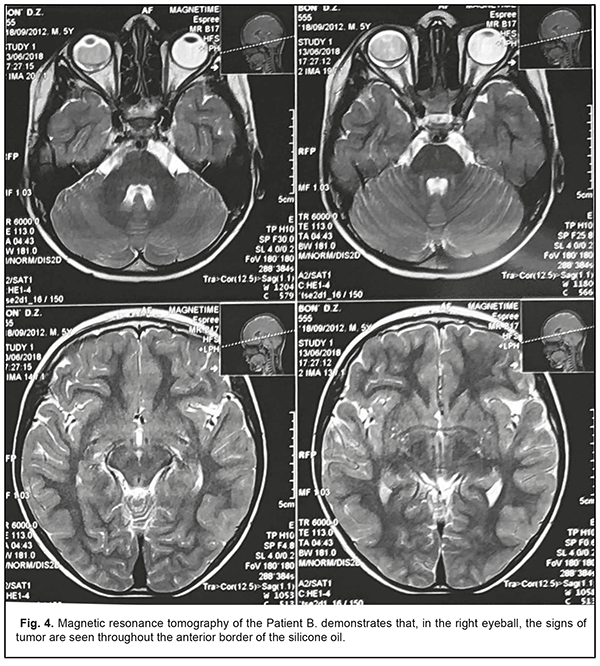

Magnetic resonance tomography, which was performed on 13 June 2018, satisfied the doubts. So, the signs of neoplasm were revealed in the right eye throughout the posterior border of the silicone oil (Fig. 4); the thickness of ocular nerves was similar on both sides (0.5 sm); no focal cerebral changes were revealed.